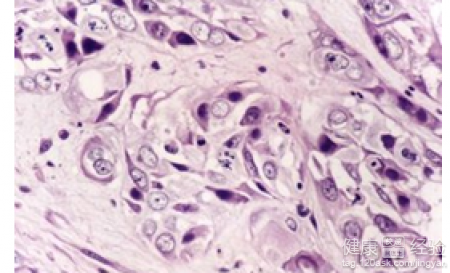

高熱驚厥是一個比較常見的疾病的,而且小兒一旦有高熱驚厥的時候,也是會有比較恐怖的症狀出現的。甚至有的家人甚至會擔心得流眼淚的。而且病人往往會在呼吸道感染以後出現的。而且一旦有其他感染性疾病的早期,也會有高熱驚厥的症狀。建議高熱驚厥的病人需要積極的治療的,而且不要給孩子亂吃藥的。幼兒高熱驚厥要做哪些檢查確診原因呢?

1高熱驚厥的孩子需要做一些急救的,而且需要進一步檢查孩子的血液的,需要看看粒細胞的情況的,所以對於高熱驚厥的孩子,那麼抽血檢測是必要的,而且需要做糞便等檢查,需要配合檢查。

2高熱驚厥是一個比較常見的疾病,需要去大醫院裡面去查找清楚病因的,而且需要進一步針對病因進行處理,一旦病人的體溫超過38度的時候,需要及時用一些退燒藥去退燒的,不要拖拖拉拉。

3有必要的時候要做腦電圖的檢查。而且可以采取物理降溫等方法控制體溫。一旦小兒發熱的時候,需要積極的退燒的,而且把溫度要控制在38.5以下,然後慢慢的隨著年齡的增長,就不會發生驚厥了.。